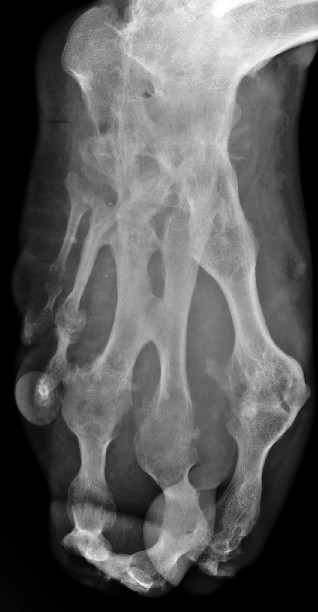

男性,35岁,左足随年龄增大,无疼痛及其它不适。还能开车了。

幼年时就大吗,如果是就是先天性畸形--巨足症。

考虑为:左足遗传性多发性骨软骨瘤并血管瘤(动脉瘤?)。

考虑先天性巨肢症(节段性肥大)。

支持!另外还有诸关节间的骨性强直。

左足个组成骨部分融合,形态失常(患者未感异常)

考虑先天病变(节段性肥大)

(左足随年龄增大,无疼痛及其它不适)考虑为多发性 内 外生骨软骨瘤。

巨足畸形合并并趾畸形。

巨趾畸形。遗传?或并发血管瘤或神经纤维瘤

符合先天性巨肢症,临床资料需完善。1\2\3跖趾骨肥大为主要表现,但骨关节形态有些失常,有部分融合,是否曾有过感染。